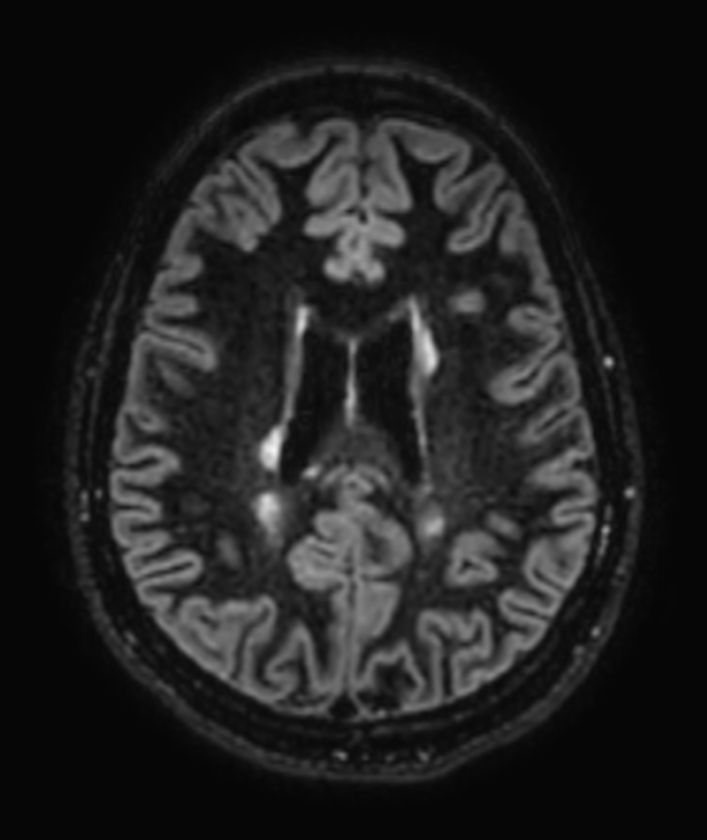

Multiple Sclerosis versus TIA

Standardized Multiple Slerosis MRI protocols typically require long scan times. Addition of Compressed SENSE enables faster exams, without compromise in image quality1. SWIp sequence has a high sensitivity to enhance contrast for deoxygenated (venous) blood or calcium deposits. This may help, when used in combination with other clinical information, in the diagnosis of various neurological pathologies. 3D (BrainVIEW) lets you acquire high resolution data in multiple directions in one scan. Isotropic voxel size enables reformats in any plane without loss of resolution.

T2w TSE MultiVane XD